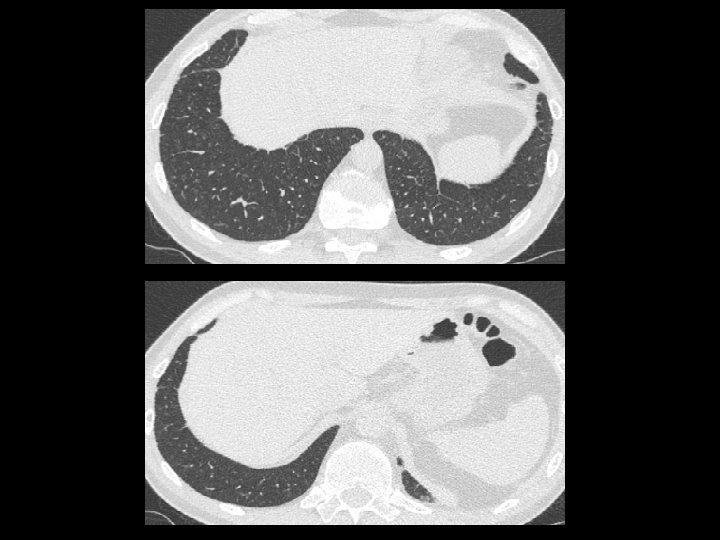

En ambos hemitórax se observan múltiples imágenes nodulillares de escasos milímetros de distribución difusa, predominando en los lóbulos superiores, de localización aleatoria En topografía del LM se observan aisladas prominencias bronquiales con sutiles cambios inflamatorios peribronquiales sin evidencia de consolidación. Pequeñas imágenes ganglionares a nivel supraclavicular en rango no adenopático. En topografía del espacio paratraqueal derecho y espacio subcarinal así como también a nivel hiliar bilateral se observan pequeñas imágenes ganglionares algunas con calcificaciones en su superficie de corte. Derrame pericárdico.

Imágenes características en tc: • Pequeños nódulos parenquimatosos distribuidos predominantemente en región peribroncovascular o en septos interlobulillares ( + frec ) • Engrosamiento septal interlobulillar(50%) • Adenopatías mediastinales (39%) • Engrosamiento paredes bronquiales (46%) • Opacidades en vidrio esmerilado (32%) • Patrón en panal de abeja (7%)

Opacidades nodulares, bronquiolectasias nódulos subpleurales